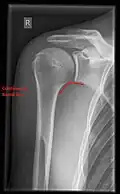

X-ray

Projectional radiography views of the shoulder include:

- AP-projection 40° posterior oblique after Grashey

The body has to be rotated about 30 to 45 degrees towards the shoulder to be imaged, and the standing or sitting patient lets the arm hang. This method reveals the joint gap and the vertical alignment towards the socket.[26]

- Transaxillary projection

The arm should be abducted 80 to 100 degrees. This method reveals:[26]

- The horizontal alignment of the humerus head in respect to the socket and the lateral clavicle in respect to the acromion

- Lesions of the anterior and posterior socket border, or of the tuberculum minus

- The eventual non-closure of the acromial apophysis

- The coraco-humeral interval

-

CR. shoulay film. -

Transaxillary conventional radiography -

Y-projection conventional radiography